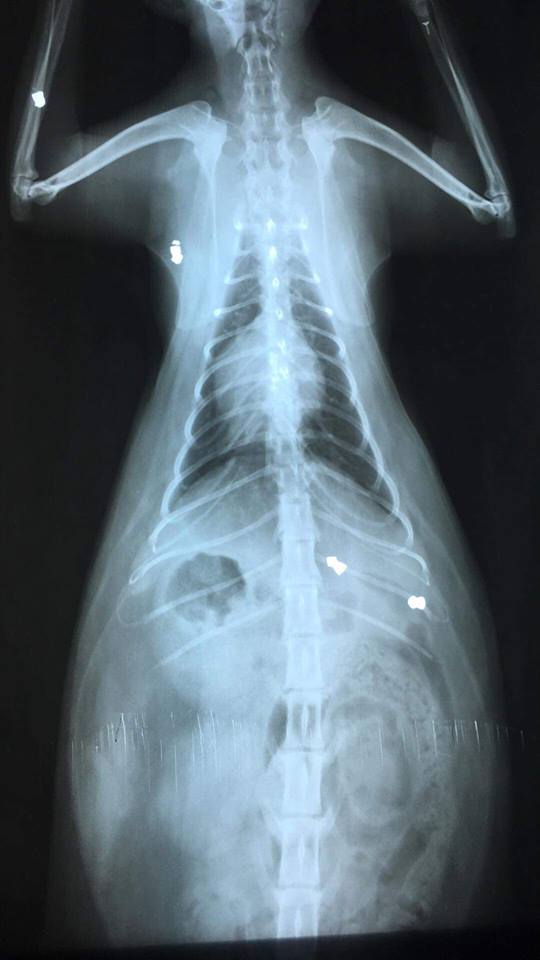

Strona główna Ktoś strzela z wiatrówki do zwierząt przych wet 2

przych wet 2

przych wet 1